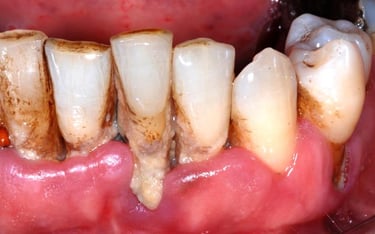

Gum disease treatment may be nonsurgical or surgical, depending on the stage of disease and your oral and overall health. Nonsurgical treatments include scaling and root planing and antibiotics. Surgical options include pocket reduction surgery and guided tissue regeneration

What is gum disease treatment?

Gum disease occurs when plaque and tartar build up on your teeth surfaces. Your gums react to the bacteria in these irritants and become red, swollen and tender. Your gums may also bleed when you brush or floss.

The sooner you treat gum disease, the better chance you have for long-lasting oral health. At its earliest stage (gingivitis), gum disease is reversible. But the later stages (periodontitis) damage your gums and underlying bone. This results in gaps — or periodontal pockets — around your teeth, leading to further infection, loose teeth and even tooth loss.

Dental prophylaxis

Dental prophylaxis is a routine dental cleaning — like the one that many people have with their hygienist twice a year. During this procedure, a provider removes plaque and tartar from your teeth surfaces.

Surgical gum disease treatments

Removing the tartar buildup and clean your root surfaces. Smooth and reshape areas of damaged bone, making it harder for bacteria to hide and grow. Finally, we reposition your gums and suture them into place.